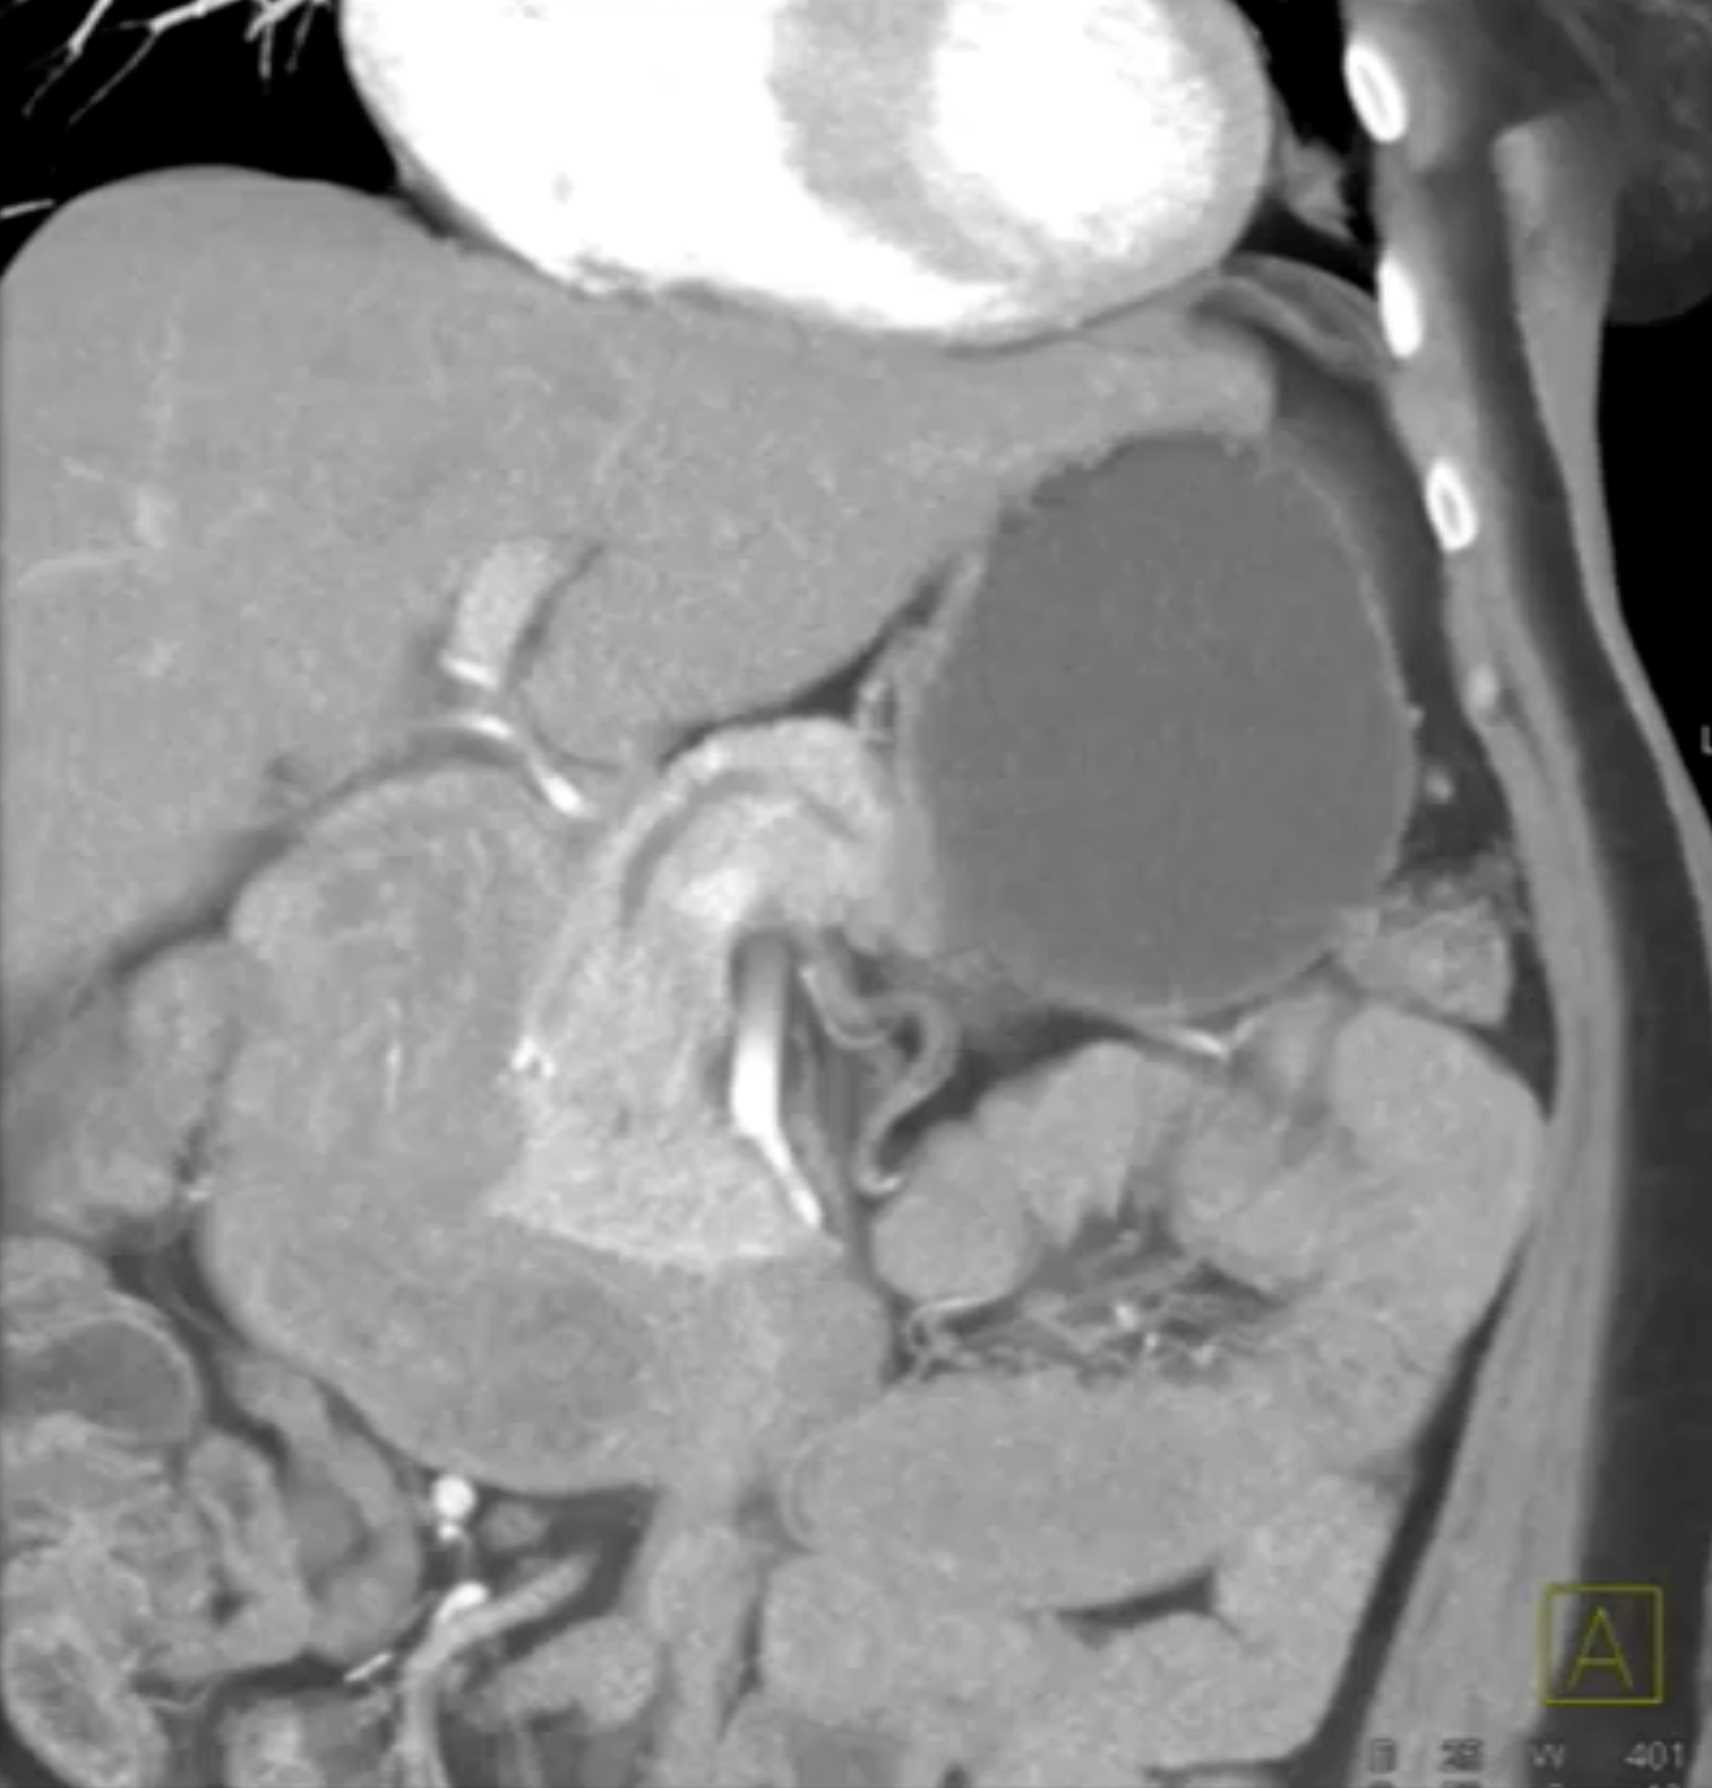

Lagre Gastric GIST Tumor